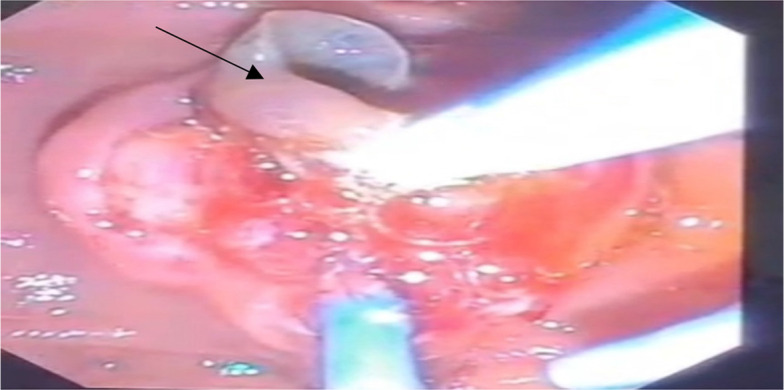

Here we report biliary fascioliasis in two women 27 and 54 years old from Ardabil Province, Iran who presented with nausea, anorexia, weight loss, and pain between shoulder blades. Endoscopic ultrasound showed distal common bile duct strictures (CBD) and a lesion in its proximal. Endoscopic retrograde cholangiopancreatography (ERCP) was performed and live parasites were diagnosed and successfully managed into the duodenal lumen. The clinical findings of the patient improved after the procedure. This report emphasizes that the prevalence of Fasciola in Ardabil is predictable and this infection could be simultaneously diagnosed and treated by the ERCP.